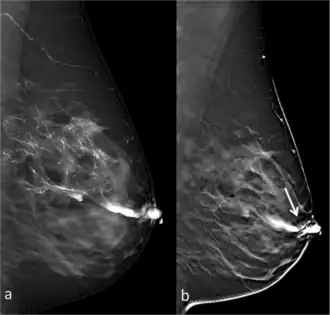

Full-field digital (FFD)-galactography (left) and Digital breast tomosynthesis (DBT)-galactography (right) showing intraductal papilloma.

Galactography or ductography (or galactogram, ductogram) is a medical diagnostic procedure for viewing the milk ducts. The procedure involves the radiography of the ducts after injection of a radiopaque substance into the duct system through the nipple. The procedure is used for investigating the pathology of nipple discharge.

Galactography is capable of detecting smaller abnormalities than mammograms, MRI or ultrasound tests. With galactography, a larger part of the ductal system can be visualized than with the endoscopic investigation of a duct (called galactoscopy or ductoscopy).